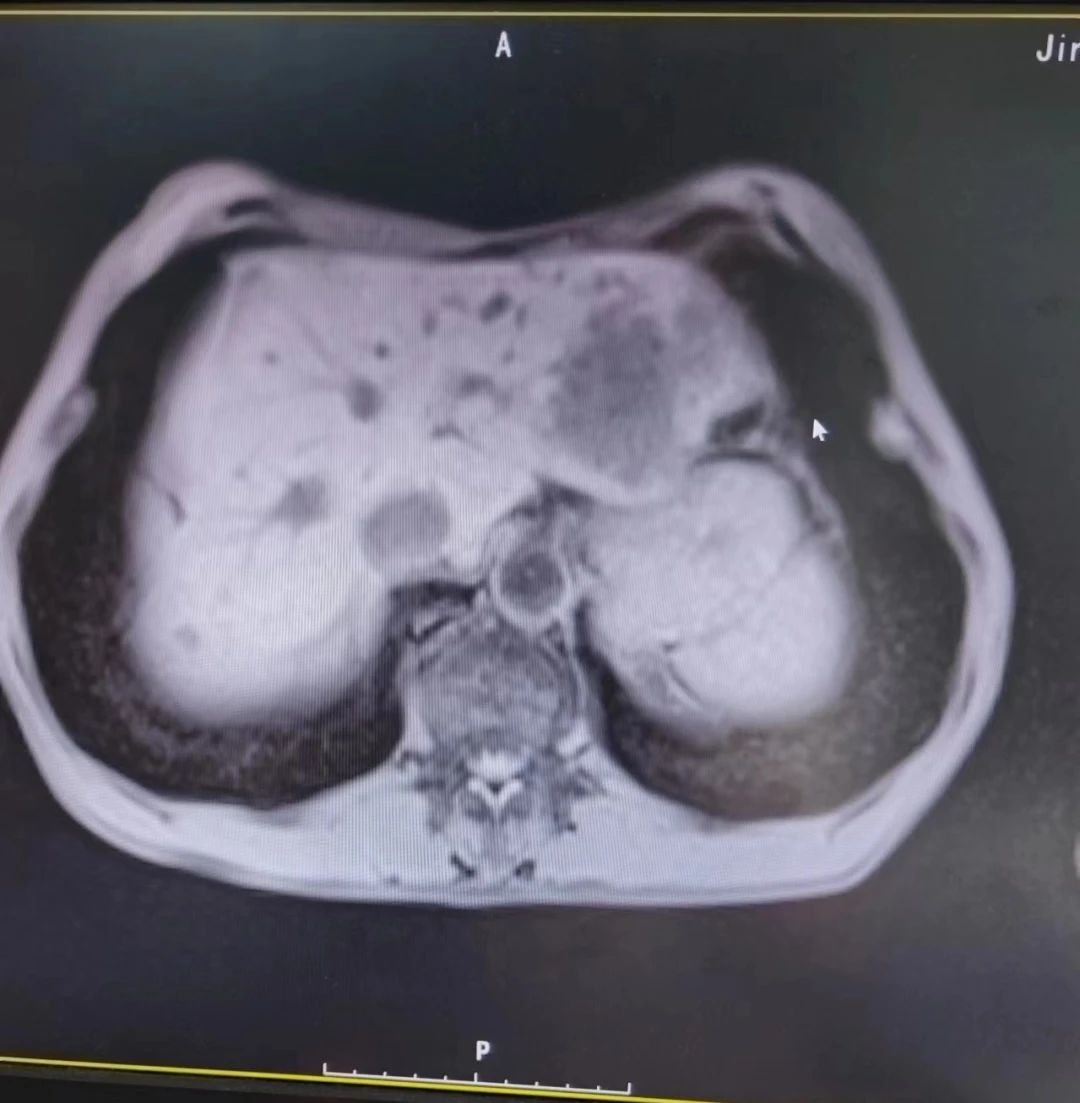

年近七旬的陈大爷,感觉肛门疼痛伴有坠胀已经半年多了,他怀疑自己得了痔疮,经亲戚朋友多方打听,从枣庄来到济南市槐荫人民医院看病。李兆德主任在门诊接诊了这位患者,经过详细的问诊和初步检查,判断这位患者不是普通的痔疮。在李主任的建议下,老人立即入住肛肠四科。入院后,老人做了超声、磁共振以及肠镜检查,诊断结果不容乐观:患者肠道内有多个息肉,而且在直肠上发现了肿物,磁共振结果显示肿瘤已经在肝部发生了转移。

“这位患者已经69岁,还伴有肠梗阻、肺气肿、多发结肠息肉等多种疾病,肝部的肿瘤直径达到6厘米,像一个小土豆,治疗起来难度不小”,肛肠四科桑温昌主任立即向医务科提出重大手术申请,医务科主任王冰建议充分术前准备,多学科会诊。桑温昌邀请神经内科朱连英主任、手术麻醉科陈丽丽主任、保健内分泌科黄晓真主任、重症医学科王大兴主任、神经外科杜池刚主任、急诊医学科肖振东主任等专家进行会诊,各学科专家进行了周密、细致地讨论,制定详细的手术方案和流程;针对手术中可能出现的一系列问题群策群力,做好最佳预案,尽最大努力确保手术成功。